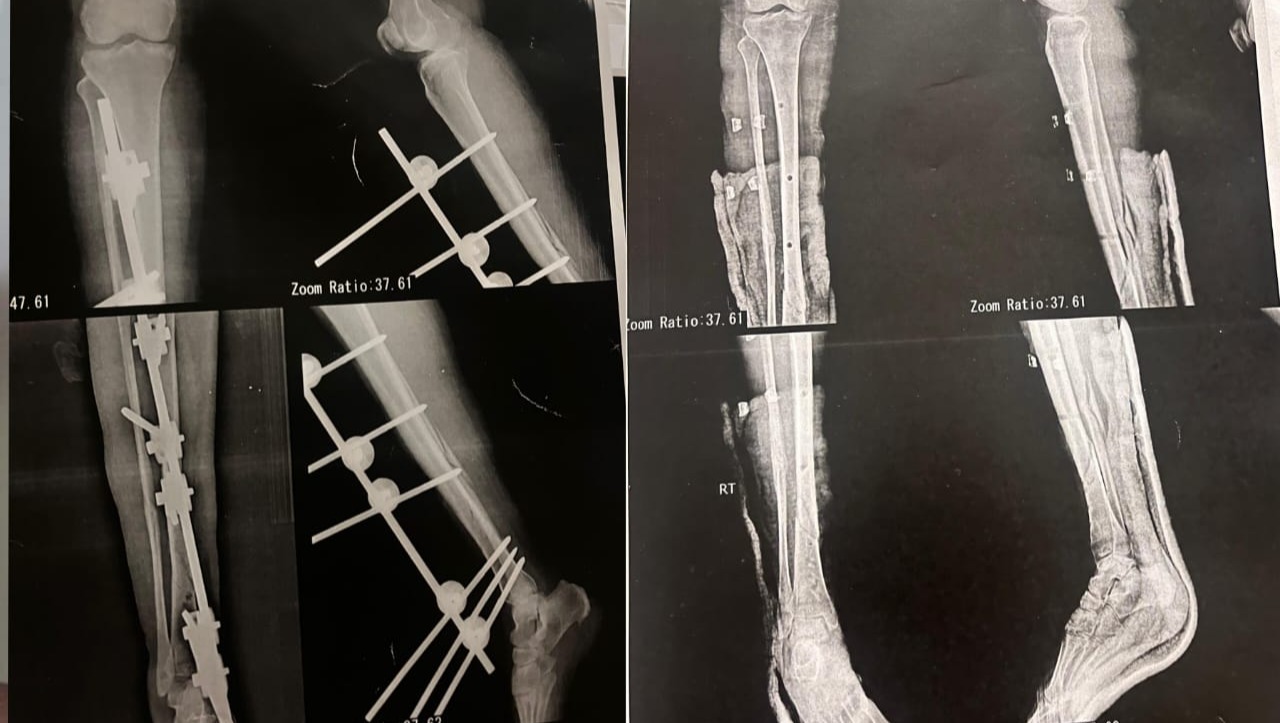

Her mother’s leg before and after plate insertion which was the first step they took in treatment: